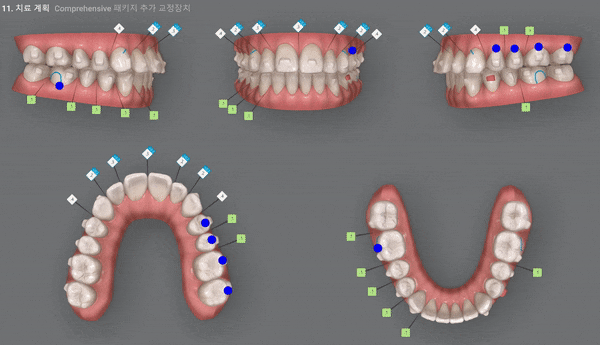

환자분께서는 인비절라인의 Comprehensive Package로

5년동안 재스캔하여 원하는 만큼 장치를 받아 인비절라인의 추가제작이 가능하시답니다.

첫번째 클린체크가 끝나고 개방교합이 벌써 많이 개선되었습니다.

이어 두번째 클린체크를 확인해 보실게요~!

두번째 클린체크

29개의 인비절라인 장치 완료 후 치아상태, 개방교합 개선됨

Final ClinCheck

두번째 클린체크는 11개의 장치를 통해 클린체크를 마무리 했습니다.

첫번째 클린체크에 이어 좀더 디테일한 부분까지 어금니 교합과 앞니 배열등 미세한 부분을 상호 보완, 개선하여 교정치료를 마무리 하셨는데요.

전체적으로 위 아랫니의 교합이 제 위치를 찾으며 정중선이 일치하도록 마무리를 해드렸습니다.